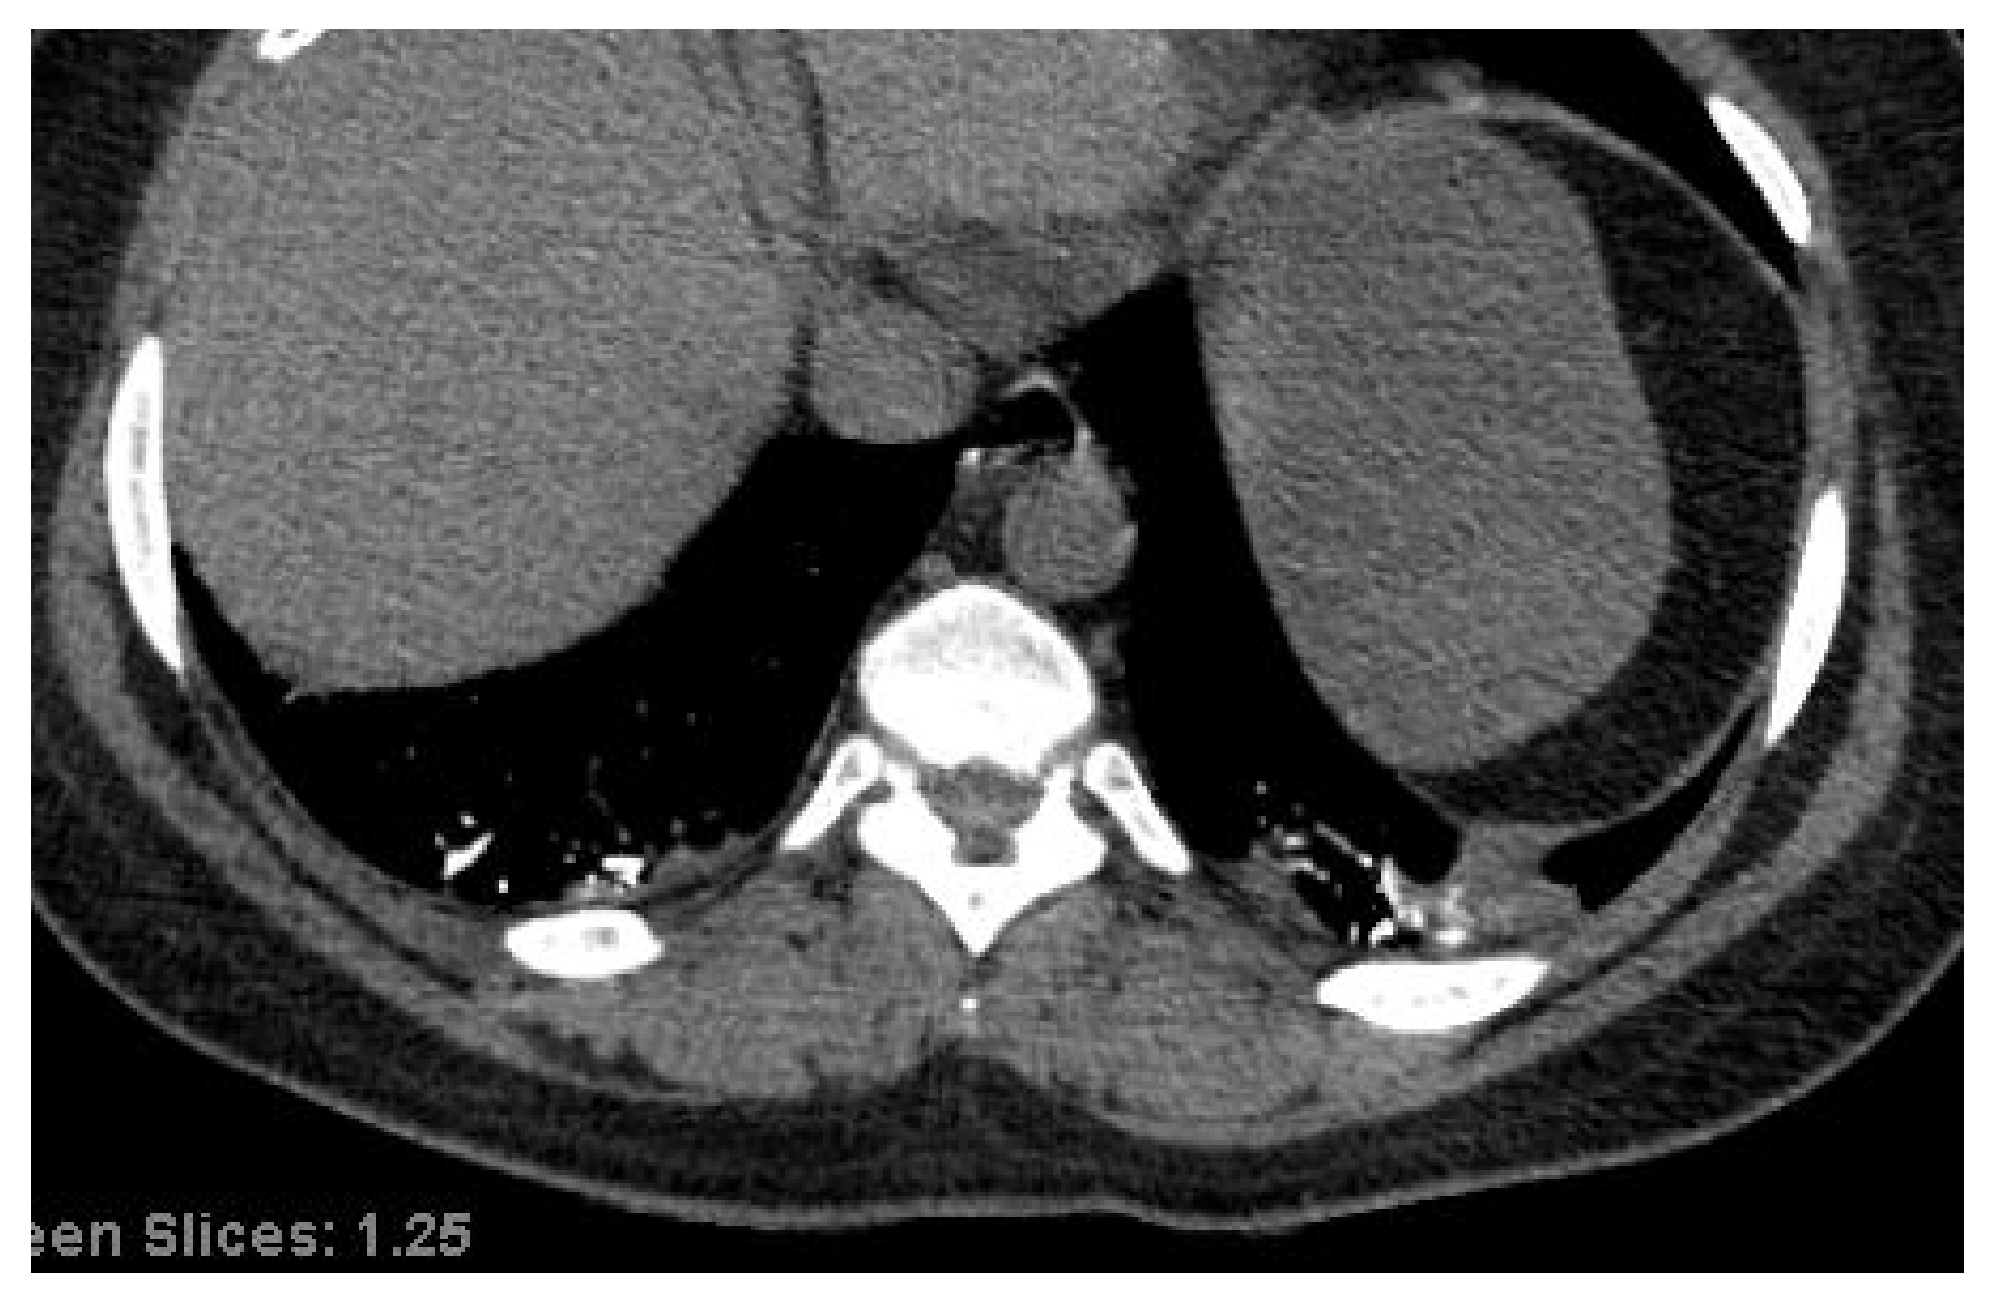

3.2. Chest CT Scans Performed in the Acute Phase (0–4 Days)

3.3. Chest CT Scans Were Performed in the Subacute Phase (5–12 Days)

4.1. Endothelial Dysfunction